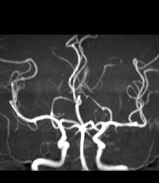

1.4 磁共振成像MRI

1946年美国Stanford大学 Felix Bloch和Harvard大学的 Edward Purcell各自独立行磁共振现象研究,1952年他们荣获诺贝尔物理学奖。MRI应用逐渐扩展,在医学诊断中被认为是最重要的进展。

MR是一种生物磁自旋成像技术,它是利用原子核自旋运动的特点,在外加磁场内,经射频脉冲激后产生信号,用探测器检测并输入计算机,经过计算机处理转换后在屏幕上显示图像。